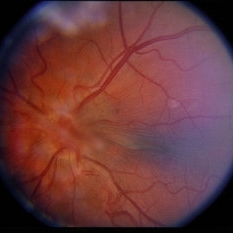

Retinal Capillary Hemangioblastoma

Optic nerve in this eye with fibrosis over the nerve and posterior pole.

Condition/keywords: retinal capillary hemangioblastoma